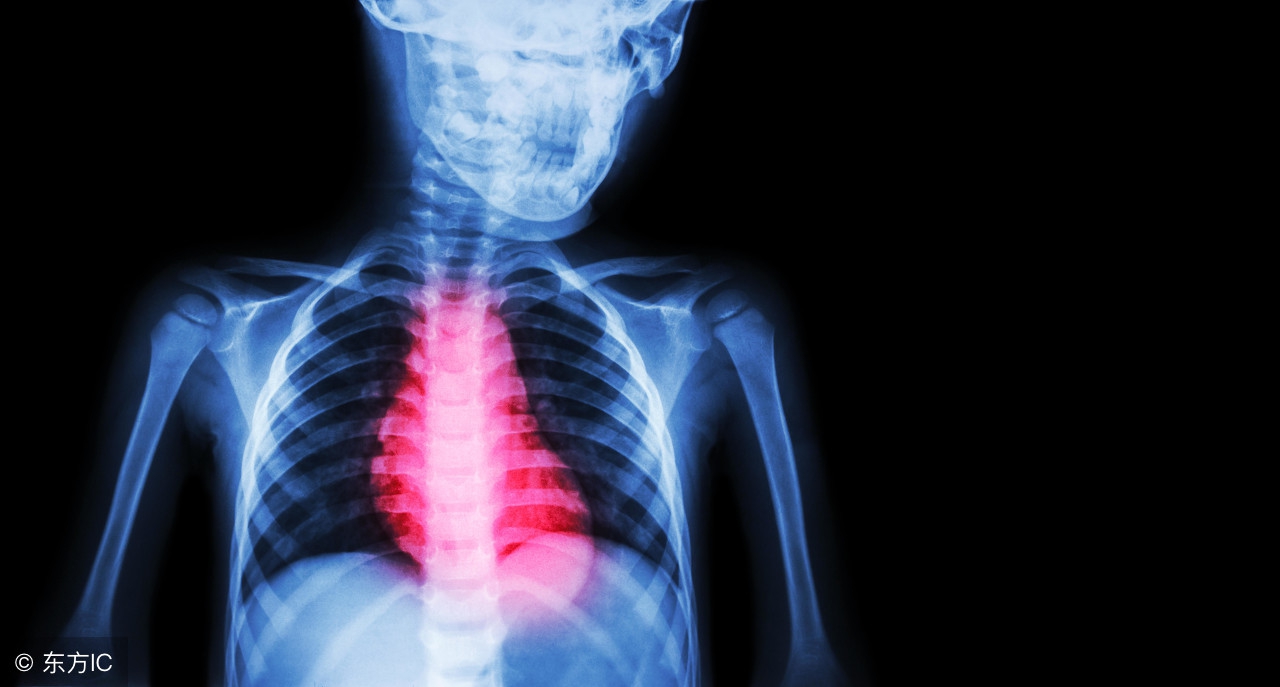

随着生活节奏的逐渐变快,各种心脏病的发生率越来越高,尤其是心肌缺血心肌缺血对心脏和全身都可能带来许多不利影响。生活当中很多老年人比较容易患上心肌缺血,但随着亚健康的人们也是愈来愈多,一些年轻人也出现心肌缺血的表现。因此心肌缺血的预防至关重要。